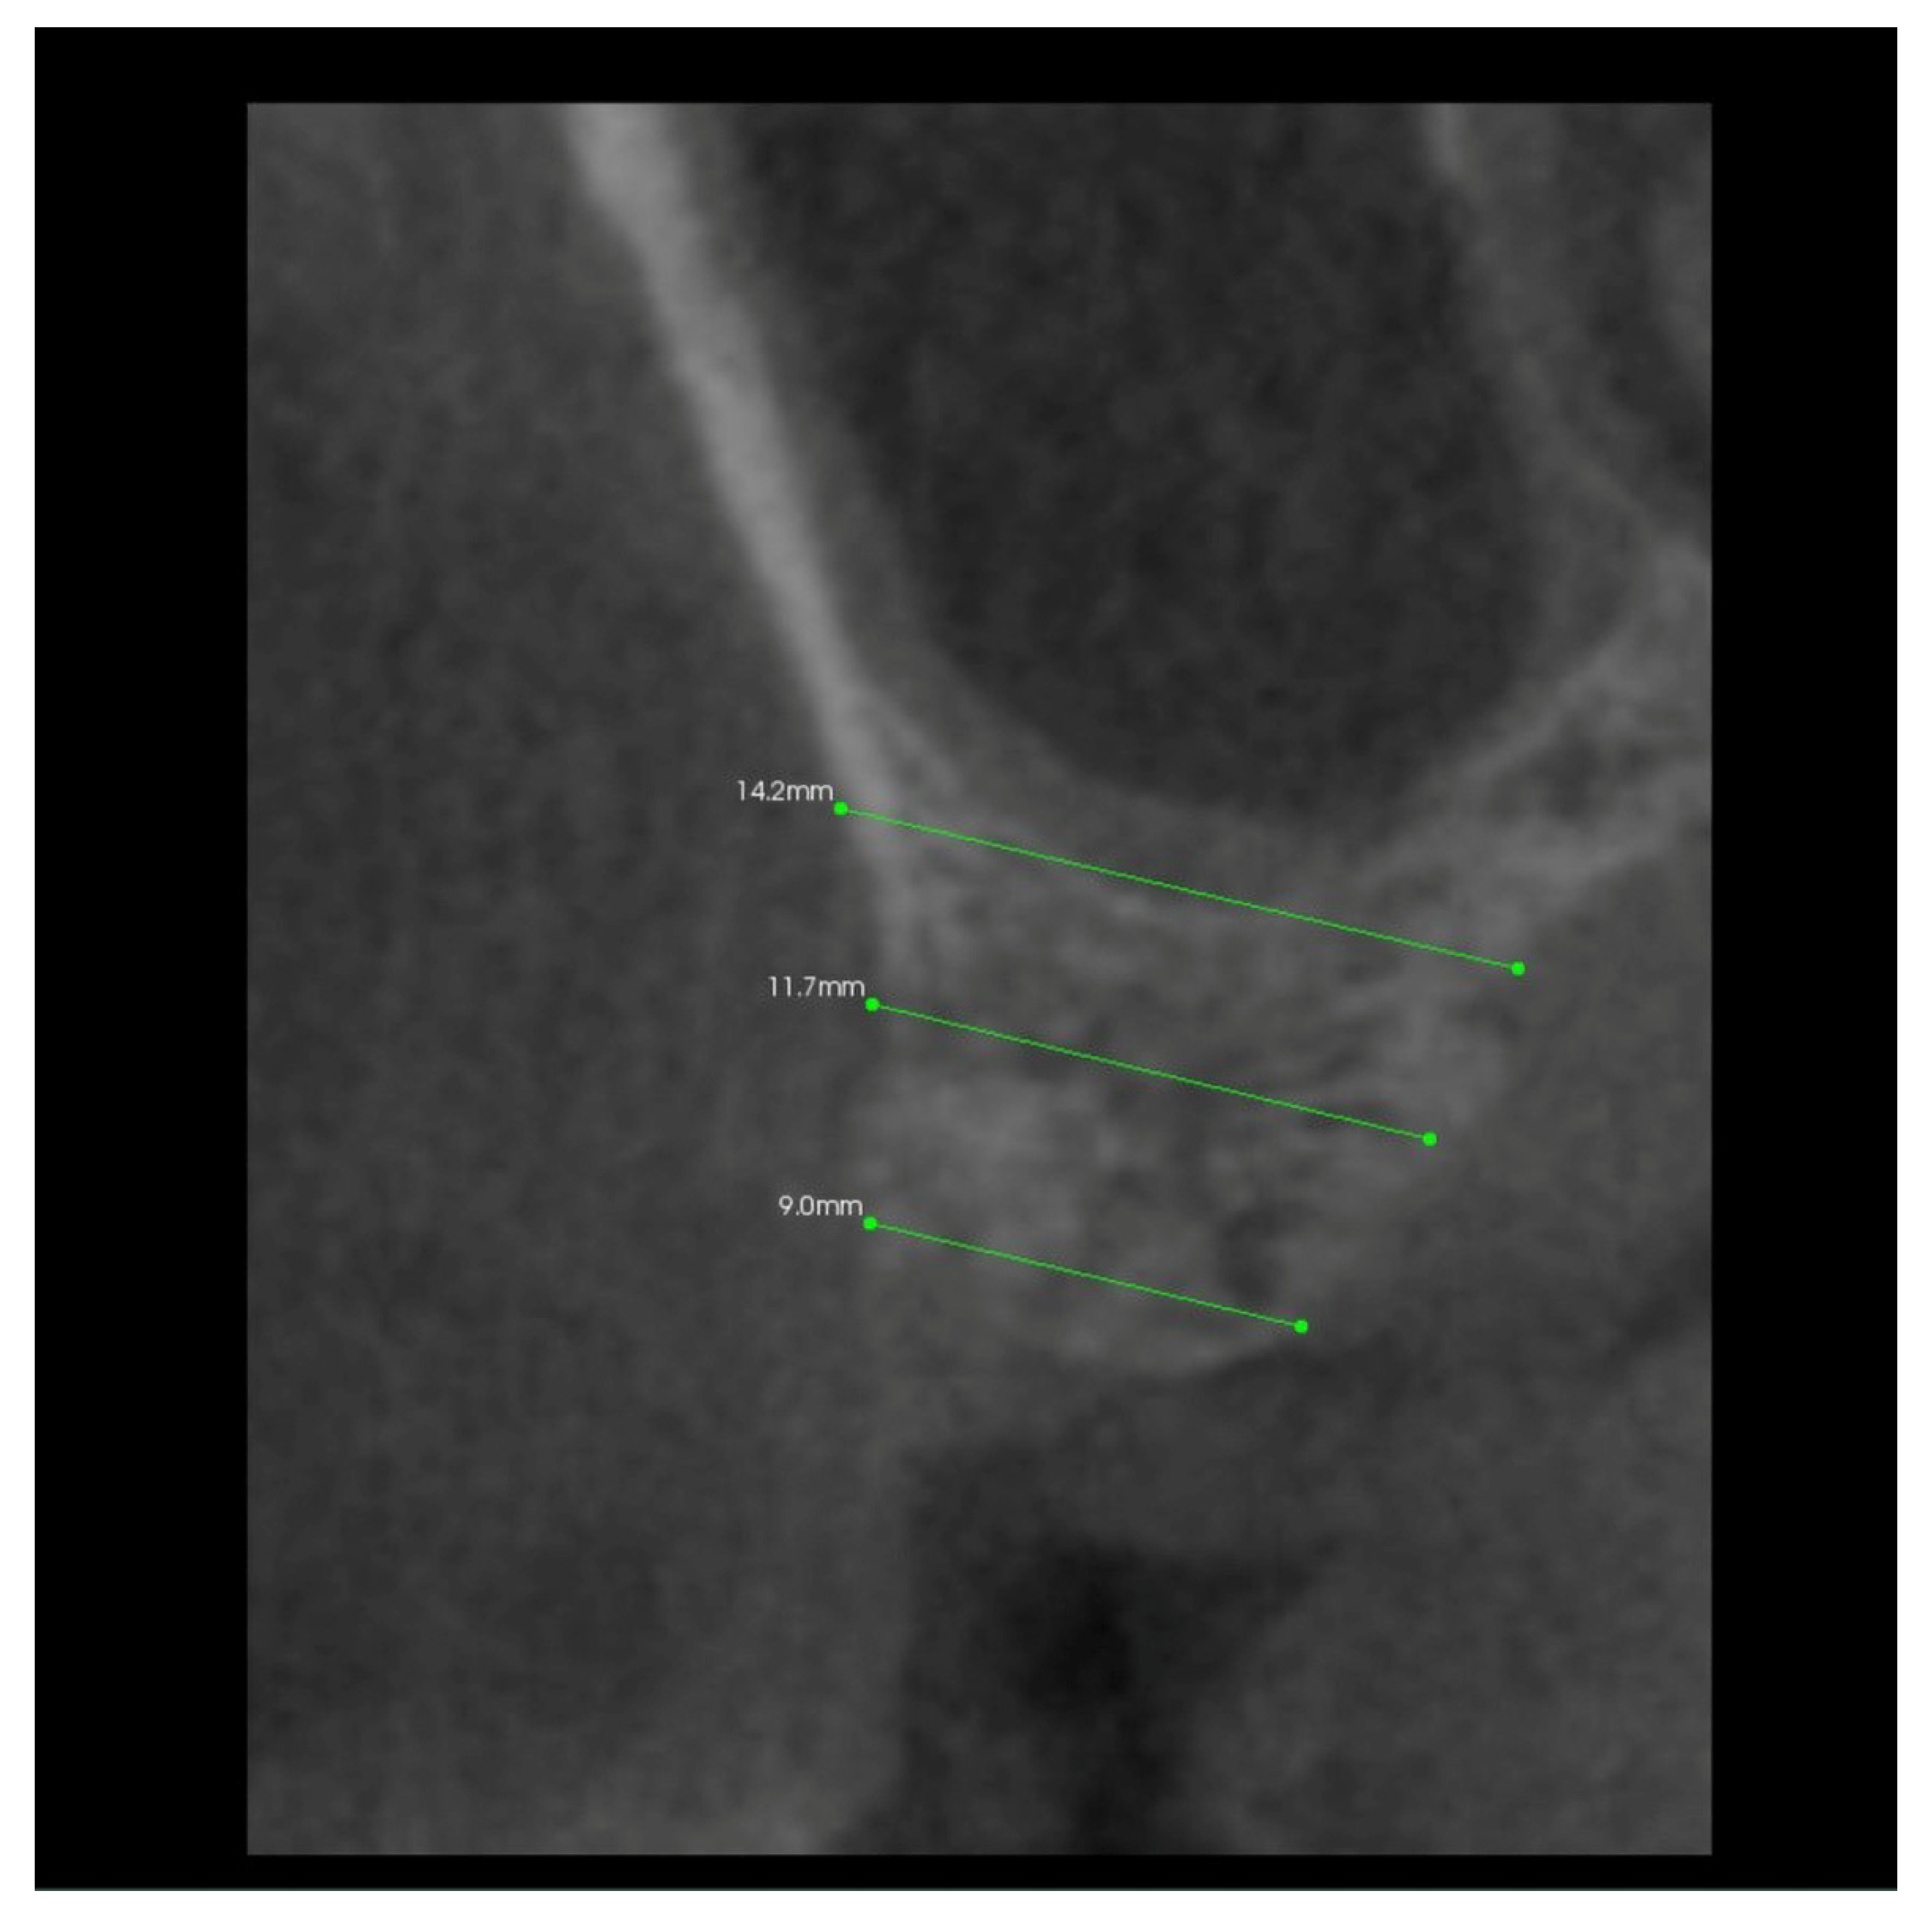

In addition, 6 months after the surgery, another performance of volumetric CBCT limited to the area of the post-extraction alveoli using the Kodak 9000 apparatus was recommended. During these examinations, the alveolar process in the extraction site and grayscale values in the selected measurement points were measured (Figure 6, Figure 7, Figure 8 and Figure 9).

Figure 7.

Transverse imaging of mandibular alveolus obtained from CBCT. The alveolus width measurement 10 days post-extraction.